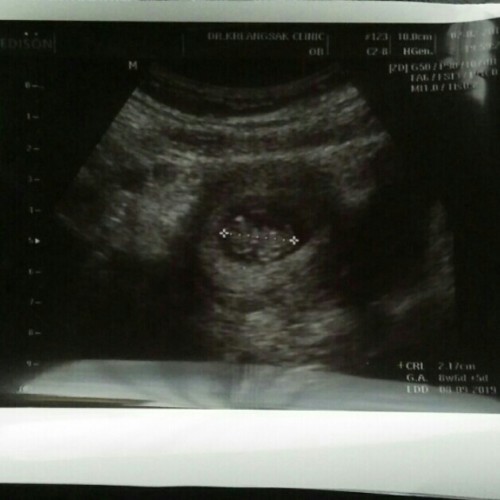

อัลตร้าซาวด์

ขอดูภาพอัลตร้าซาวด์ตอน9วีคหน่อยค่ะ พอดีจะไปซาวด์

ตอน 9weekคะ ตอนนี้ 16week แล้วคะ

ในรุป11w2d..ตอนนี้12w3dแร้วค่ะ

10วีค กับอีก2วันค่ะ

ตอน9w 6dคะ ตอนนี้24wแล้วคะ